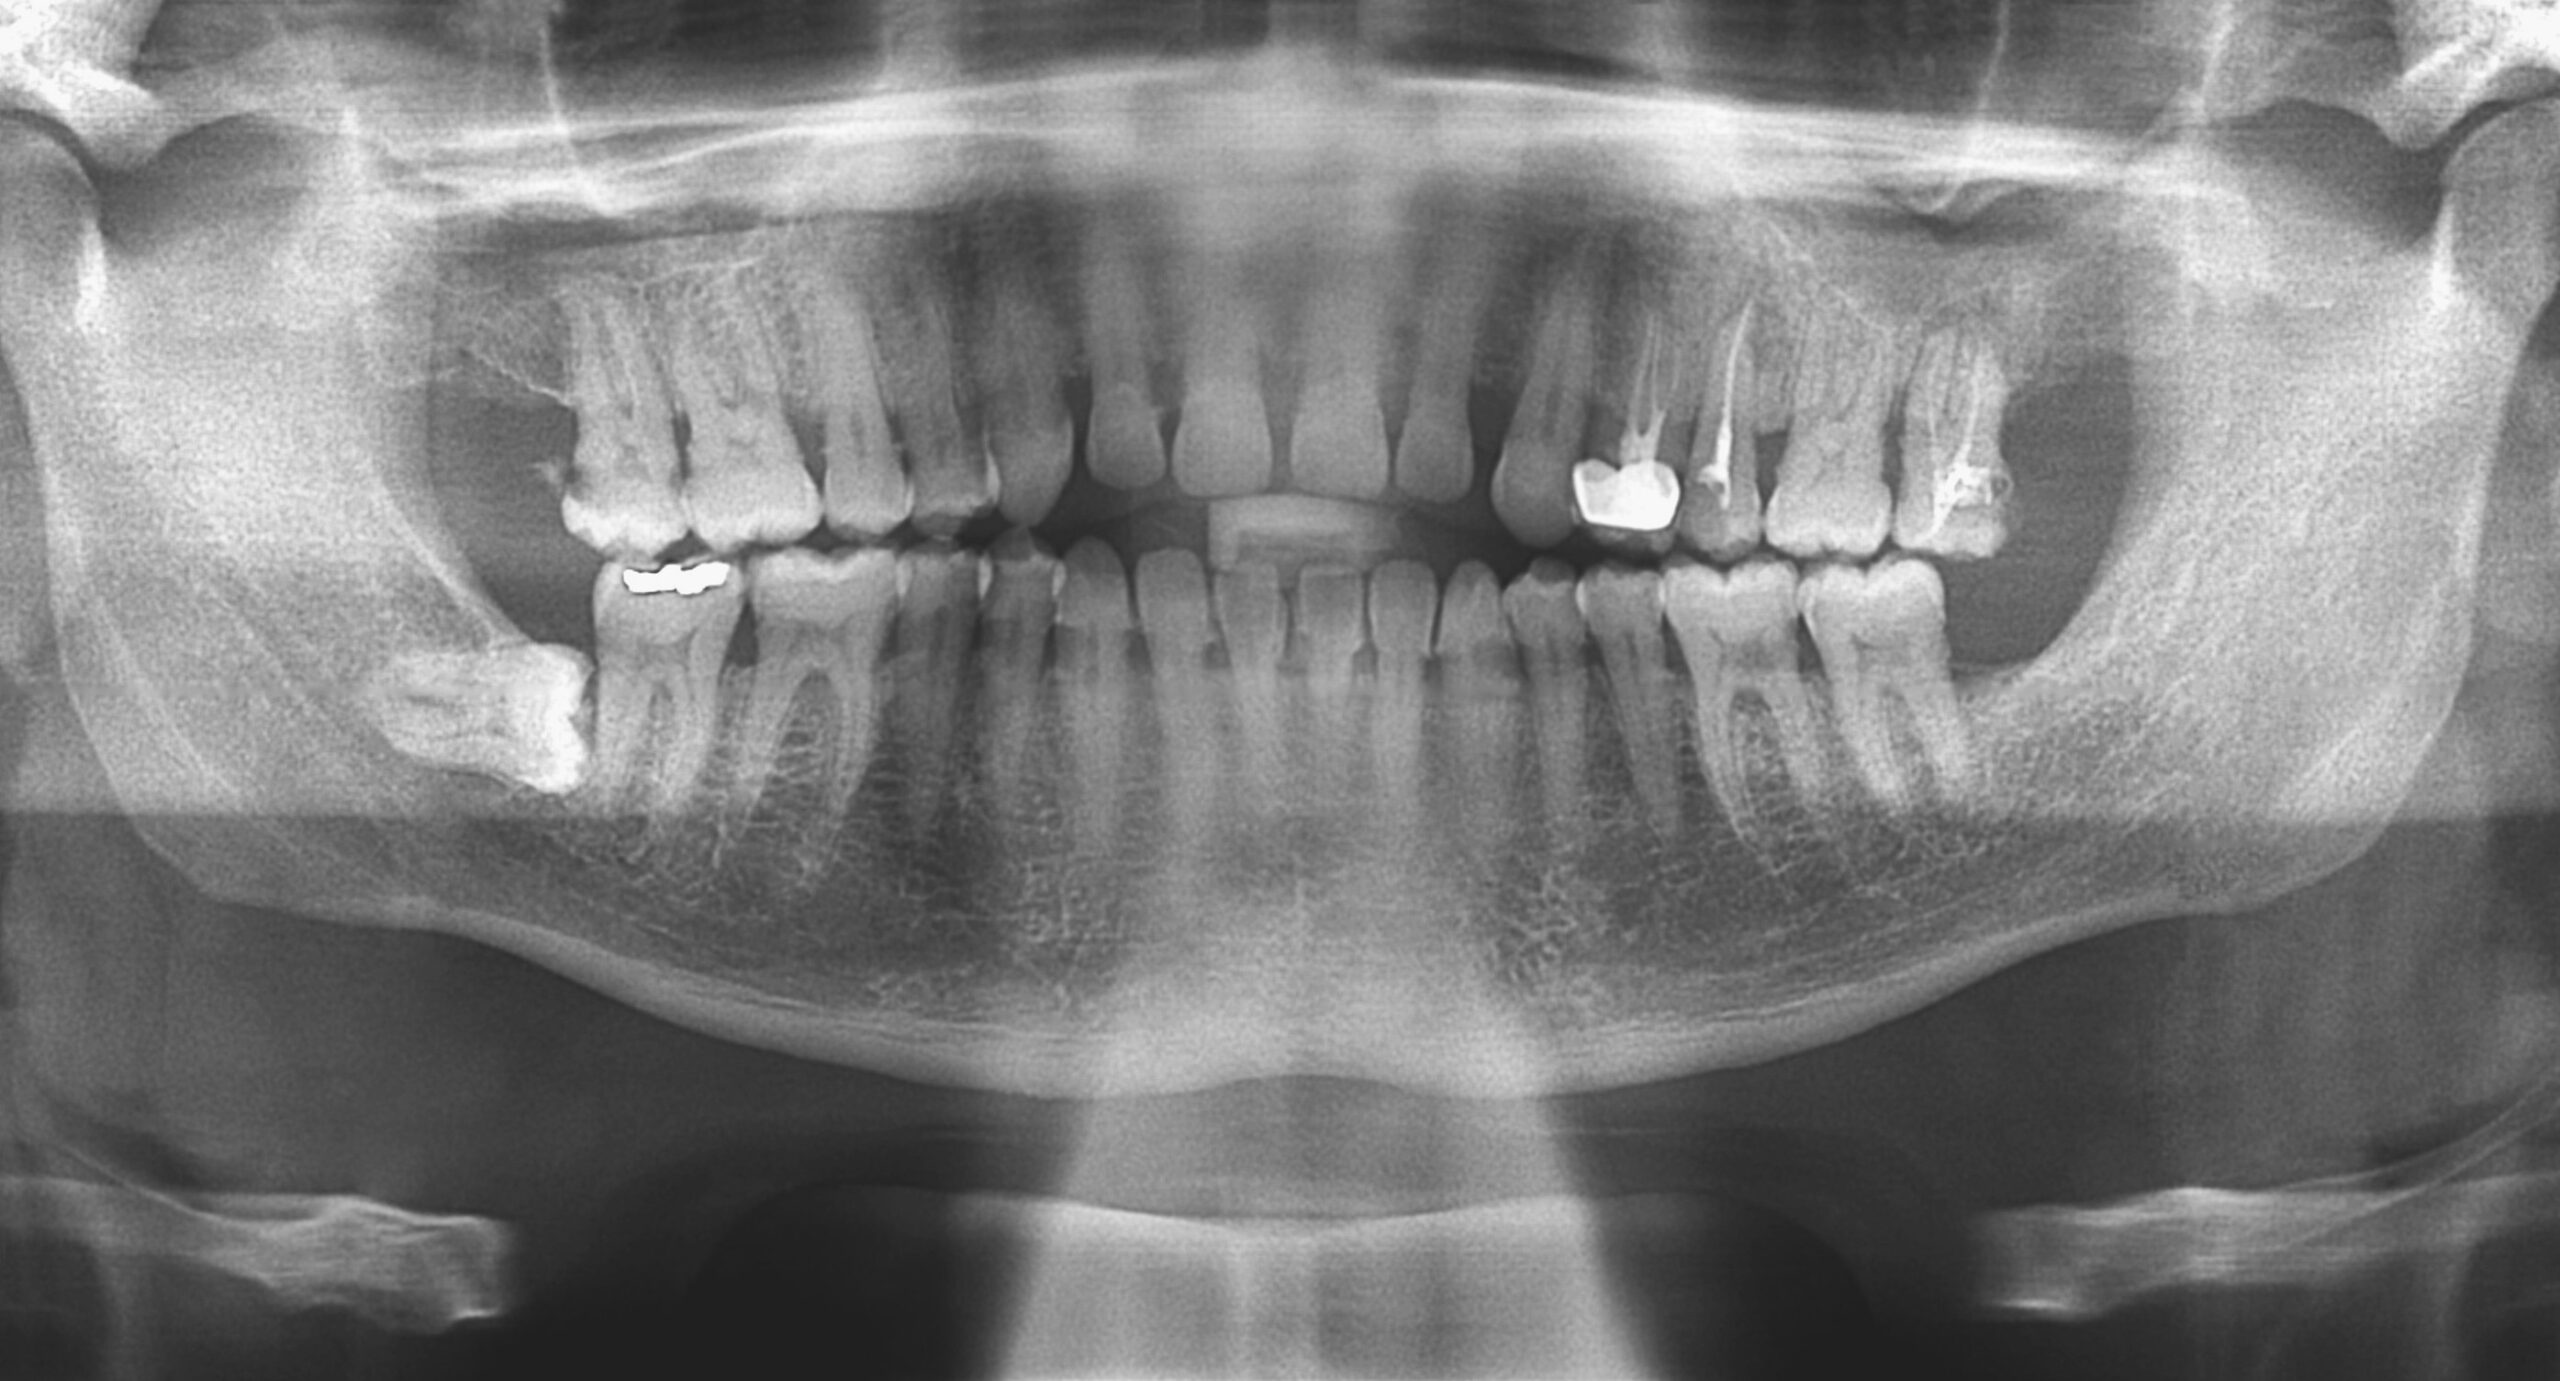

親知らず抜歯とスポーツパフォーマンスの関係

本日はスポーツをしている方にとって、親知らず抜歯はどんな影響があるのか?についてお伝えします。

1. 親知らずと全身コンディション

親知らずは正しく生えていないと、炎症や膿を繰り返すことがあります。

この炎症は口の中にとどまらず、免疫機能の低下や慢性的な疲労感につながることもあります。

特にアスリートや運動習慣のある方にとっては、練習や試合パフォーマンスに直結する大きな問題です。

3. スポーツ歯科から見た親知らずの意味

スポーツ歯科の観点では、噛み合わせや顎関節の安定はパフォーマンスに影響すると考えられています。

不安定な親知らずがあると、知らず知らずのうちに力の伝達や集中力が妨げられるケースもあります。

長期的に見れば、親知らずの抜歯は 「身体のコンディションを整える一つのメンテナンス」 と言えるでしょう。